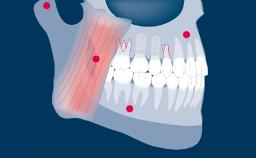

Implant-supported fixed dental prostheses aim to provide replacements for missing teeth that are able to withstand functional demands and accurately mimic the esthetics of the missing dental units.

To achieve this goal, the clinician must select the best available materials to meet the challenges posed by the clinical situation.

- identify specific situations where special care should be exercised in selecting materials for implant-supported FDPs